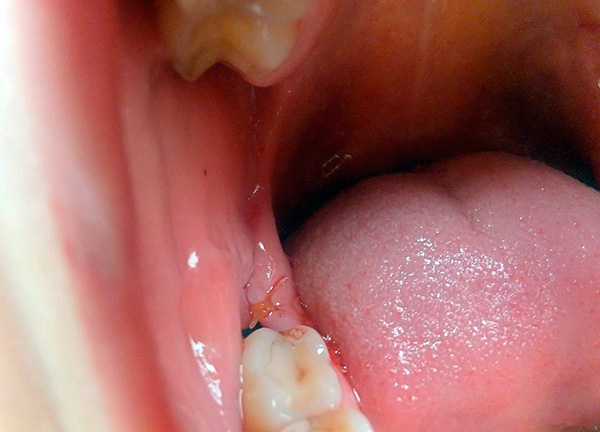

Ora supponiamo che l'ottavo dente abbia attraversato la barriera ossea e che parte della sua corona sia già uscita dalle gengive. A prima vista, può sembrare che il più difficile sia dietro: il dente è quasi tagliato, rimane solo un po '. Tuttavia, in realtà, le cose potrebbero non essere così rosee.

La seguente foto mostra un esempio di un dente del giudizio semi-rinforzato:

Spesso sotto il cappuccio gengivale si accumulano particelle di cibo e batteri, si verifica un processo infiammatorio: la pericoronite. Quando un essudato purulento si forma sotto la gomma, compaiono sintomi che ostacolano la normale vita di una persona: gonfiore nell'area del dente del giudizio, cattive condizioni generali, febbre fino a 38-39 ° C, incapacità di masticare e persino aprire normalmente la bocca, dolore severo, spesso pulsante e irradiante a vari sezioni del viso.